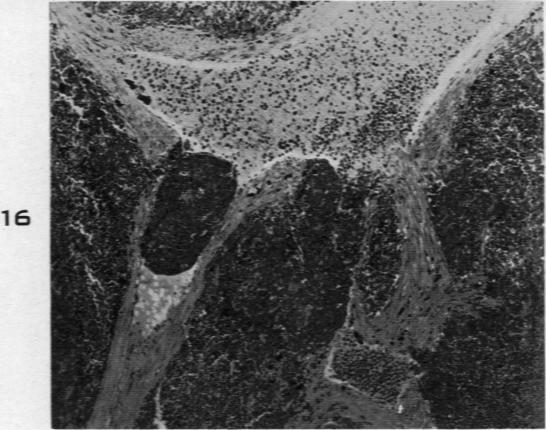

Malignant Lymphoma (So-Called Leukemia) in Dogs.

Am J Pathol. 1945 Jul;21(4):683-715.